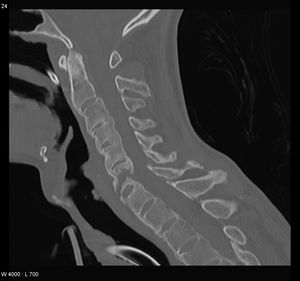

التهاب الفقار المقسط أو اللاصق Ankylosing spondylitis باليونانيةankylos, stiff; spondylos, vertebrae), تسمى قديماًBekhterev's disease, Bekhterev syndrome, و Marie-Strümpell disease هو نوع من التهاب المفصل في العمود الفقري. وهو يسبب تورماً بين الفقرات، والفقرات هي الأجزاء الأسطوانية التي تكون العمود الفقري، كما يسبب تورماً في المفاصل بين العمود الفقري والحوض. إن التهاب الفقار المقسط أو اللاصق هو أحد أمراض المناعة الذاتية. إن الجهاز المناعي المسؤول عن حماية الجسم من العدوى يقوم بمهاجمة أنسجة الجسم نفسها في حالة أمراض المناعة الذاتية. ويكون التهاب الفقار اللاصق أكثر انتشاراً وخطورة عند الرجال. وكثيراً ما يكون مرضاً ينتقل عن طريق الوراثة.[1]

ومن أعراضه المبكرة ألم الظهر والتيبس. وهي تبدأ غالباً في مرحلة المراهقة المتأخرة أو أوائل البلوغ. ومع مرور الوقت يمكن لالتهاب الفقار اللاصق أن يؤدي إلى التحام الفقرات مما يقيد حركتها. يمكن أن تتفاقم الأعراض كما يمكن أن تتراجع أو تختفي تماماً. إن هذا المرض غير قابل للشفاء، لكن الأدوية يمكن أن تهدئ الألم والتورم والأعراض الأخرى. ويمكن أن تكون التمارين الرياضية مفيدة أيضاً.

يبدأ التهاب الفقار المقسط في صغار البالغين بألم مبهم في أسفل الظهر، ويبوسة مديدة تالية للراحة تتحسن جزئياً بالحركة والتمارين الرياضية. ينتشر الألم إلى الاليتين والقسم الخلقي من الساقين. كما يحدث ألم في القفص الصدري بإصابة المفاصل الغضروفية المركزية فيه، وقد يكون لهذا الألم صفات جنبية، ويظهر الألم أيضاً في مفاصل قبضة القص Manubriosternal والمفاصل القصية الترقوية. إن التهاب ارتكازات الأربطة والأوتار عرض بارز وقد يكون العرض الأول. وينجم الألم عن التهاب الأصابع Dactylitis ' أو وتر أشيل، أو اللفافة الأخمصية، أو عرف الحرقفة iac أ I Crest. تكون الإصابة المفصلية بشكل الام مفصلية، أو التهاب مفاصل عديد، يصيب المفاصل الزليلة الدانية وبشكل غير متناظر كالكتفين والمرفقين والركبتين ونادرا المفاصل الصغيرة القاصية. وتترافق هذه الإصابة بيبوسة صباحية مديدة وأحياناً بتورم الا أنه من غير الشائع حدوث إصابة مفصلية تاكلية شديدة.

يحدث التهاب العنبية الأمامي في حوالي ربع المرضى، ويتظاهر بألم واحمرار وخوف من الضياء، وتكون هذه الإصابة نوبية، وحيدة أو ثنائية الجانب. يبدي الفحص السريري نقصاً في حركية العمود الفقري، مع فقد تام أو جزئي للقعس القطني الفيزبولوجي، وزيادة في الحدب الظهري. أما المظاهر المتأخرة فتشمل تحدد حركة جدار الصدر في الشهيق العميق (أقل من 2.5 سم) مع انحناء تدريجي، وثبات العمود الفقري والرأس في وضعية العطف. ويمشى المريض جاراً قدميه Shuffling Gait مع تفاوت شدة إصابة المفاصل المحيطة.[2]